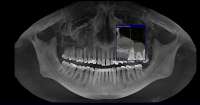

Сегодня делал обий снимок. Хуй знает, как его описать, мне выдали диск с ним, там такая хуйня, что доктор может колесиком водить-приближать-отдалять и снимок меняется, как будто 3D или хуй пойми. Мне не во что диск вставить, лол, не могу посмотреть, что там. Доктор нашла 3(!) кариеса, 1 сверху справа, второй сверху слева и третий на соседнем зубе начинающий. Причем на том зубе, который я полгода назад восстановил-нарастил. С восьмерками пока что нихуя не делать сказала, но чую, что потом они вылезут криво. Она сказала, что они будут выходить "повернутыми". Пока что еще внутри десен они(верхние).

Самая жопа в том, что под нижней 6кой, под самым корнем у меня образовалась киста(если не путаю). Док показала на компе большую черную точку. Сам зуб с удаленными каналами 12 лет назад, сказала, что залупа тебе. Или удалять или находить какого-то стоматолого с микроскопом, разбирать зуб и пытаться чистить. Пиздец, блядь.

14732846429870.jpg (43Кб, 741x273)

14732846429881.jpg (214Кб, 1280x720)

>>513868

Как и обещал. Забавно, в зеркале кажется не так криво.

Боль на третий день похожа на второй день, спасаюсь болеутоляющим. Но целом уже привык.

Вчера делал панорамный снимок. Всё как >>513480 сказал, ортодонт взял его только посмотреть. Внимание, вопрос знатокам, ортодонт посмотрел на второй пикрелейтед и сказал, что зуб в котором штифт нужно переделывать - канал не полностью залечили, а так же второй зуб - там тоже проблема с каналом и что если ставить брекеты, то им обоим придет пизда. Когда это лечить не понятно, времени в обрез, завтра пойду к своему врачу который год-полтора назад мне эти зубы лечил, послушаю что скажет. В то, что она плохо сделала не хочется верить, но нужно быть реалистом.